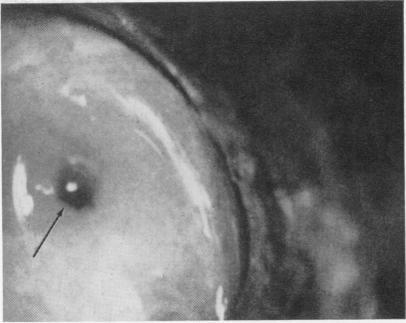

Direct observations of the canine sphincter of Oddi.

Ann Surg. 1971 Aug;174(2):264-73. doi: 10.1097/00000658-197108000-00013.